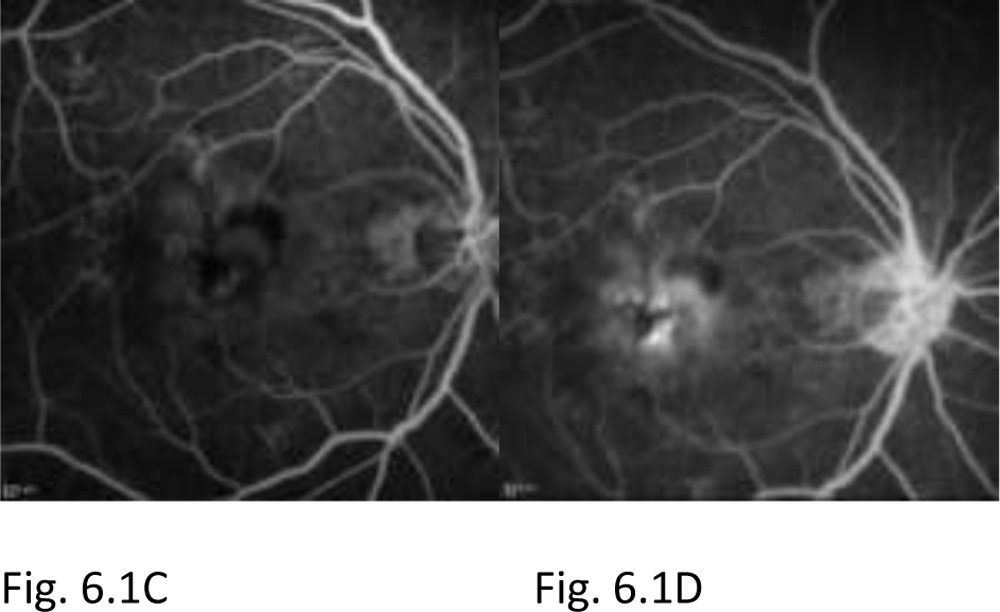

Figure 6.1:Fundus photograph OD shows greyish elevation of tissue deep to retina at macula suggestive of CNV in AMD (A). OCT of OD shows the subretinalneovascular membrane at fovea, subretinal fluid and intraretinal fluid filled cystoid spaces (B). FA of OD shows a discrete, well-demarcated focal area of hyperfluorescence at macula (arrow) in early phase frame (C), with hyperfluorescence increasing in intensity and extending beyond boundaries of hyperfluorescence identified in early phase in later phase frame (D) suggestive of a classic CNV. The visual acuity at presentation was finger counting at 3 meter.

Figure 6.2: Post 3-monthly loading dose Anti-VEGF therapy at 24 months. The patient did not develop any recurrences following the loading dose therapy, thus not requiring any further Anti-VEGF therapy. OCT of OD shows reduction in the subretinalneovascular membrane, disappearance of the subretinal and intraretinal fluid pockets, residual subretinal scar at fovea can be seen.